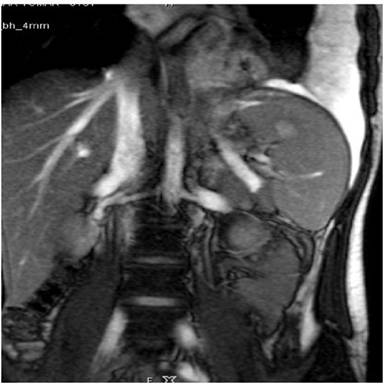

A Sixteen year old male who had sustained an injury following fall two months ago following which he had abdominal pain for 2 weeks which subsided with conservative management at local outside hospital. He presented sometime later with left sided chest pain, vague left upper abdomen discomfort, post prandial abdominal pain and significant weight loss. Chest X-ray showed a massive left pleural effusion for which he was admitted in the department of pulmonology. CT revealed a large left sided pleural effusion. There were in addition multiple ground glass opacities in both lungs and consolidation in the left lower lobe. Upper slices of abdomen revealed a focal hypodense lesion in the tail of pancreas with a small track leading to left lung consolidation through the esophageal hiatus suggesting pancreatico-pleural and pancreatico-bronchial fistula likely post traumatic etiology. The ground glass opacities in both lungs could be explained by the aspiration of pancreatic contents through pancreatico-bronchial fistula. An MRI obtained confirmed the CT findings and demonstrated a small pseudocyst communicating with main pancreatic duct and pancreatico-pleural–bronchial fistula (Figure 5). It was decided to attempt ERCP due to no significant response to conservative measures. ERCP revealed a normal cholangiogram while a pancreatogram revealed mild leakage of dye in the main pancreatic duct at the junction of body and tail of pancreas. Pancreatic duct sphincterotomy was done and a 7F 9cm straight stent was placed across the main pancreatic duct. Since actual ductal disrupton was in the tail of pancreas it could not be bridged and the stenting was purely decompressive in nature. Post ERCP period was uneventful. He was subsequently discharged and later underwent aspiration of the residual pleural fluid collection. The patient did well subsequently and underwent stent removal after six months and has not had a recurrent fluid collection in the chest or abdomen on follow up.

Figure 5. Coronal MRI image demonstrates a fistulous tract form the tail region of pancreas heading superiorly towards the left hemidiaphragm along with left pleural effusion. |